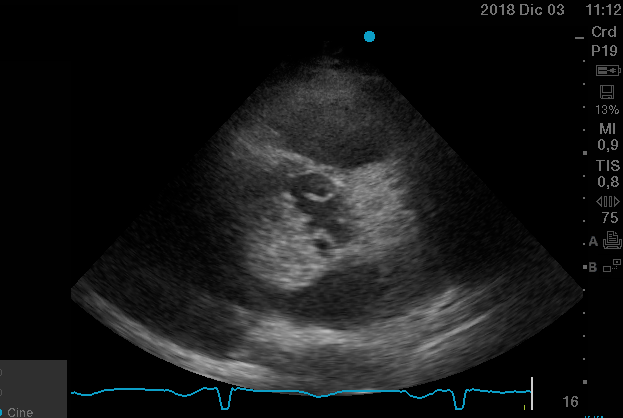

Curso de ecografía crítica en todas sus modalidades (ecocardiografía transtorácica y transesofágica, ecografía pulmonar, vascular, cerebral, FAST) dirigido a: médicos intensivistas, emergenciólogos, anestesiólogos, internistas, médicos de familia, neumólogos, cardiólogos y a todo aquel interesado por utilizar la ecografía como parte del examen físico del paciente crítico.

En nuestro afán por seguir el trabajo empezado hace ya varios años desde Europa (España) por impulsar la ecografía crítica para intensivistas, emergenciólogos, anestesistas, internistas, subespecialistas de obstetricia crítica, neumólogos y todo aquel médico interesado en aprender a utilizar la ecografía como parte de su examen físico, ahora desde Centroamérica (Panamá), hemos escrito el primer libro Latinoamericano-Europeo de ecografía crítica sub-especializado y dedicado exclusivamente al paciente con shock de cualquier etiología (obstructivo, distributivo, cardiogénico, hipovolémico) que involucra todas las modalidades ecográficas: ecocardiografía, ecografía pulmonar, vascular, abdominal, del sistema nervioso central/doppler transcraneal, etc) en el que participan muchos expertos en sus respectivas áreas tanto de Europa como de América y también algunos profesores del EDEC (Diploma Europeo de ecocardiografía / ESCIM- Sociedad Europea de Medicina intensiva).